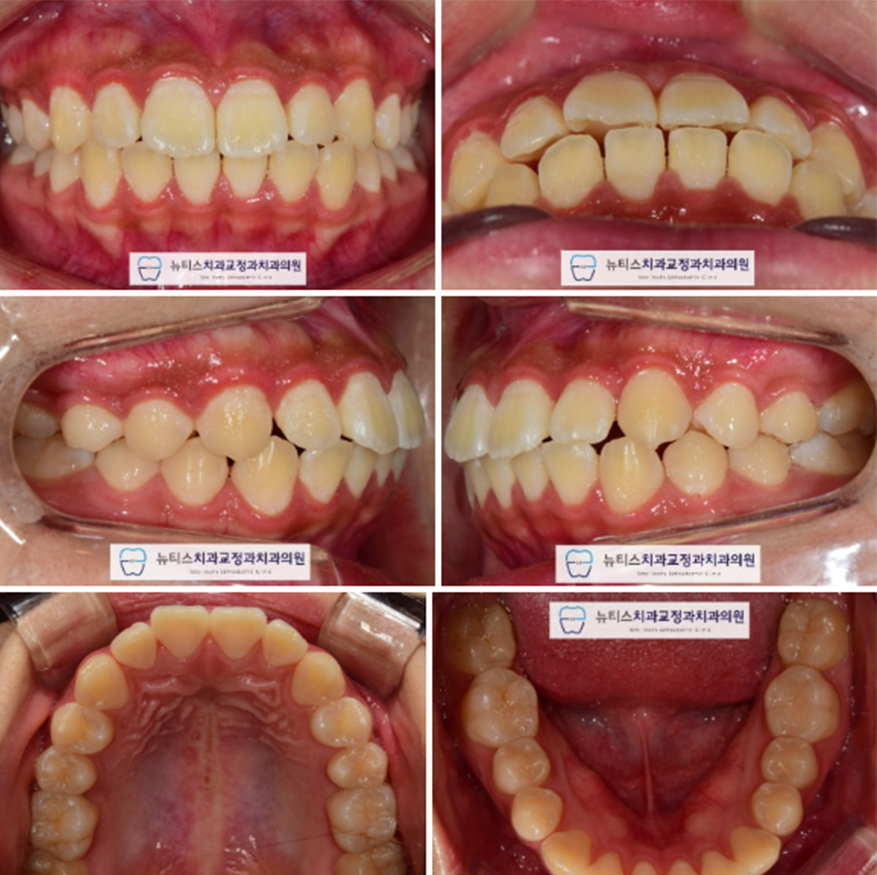

ÃÊÁø »çÁøÀÔ´Ï´Ù.

Ä¡¾ÆÀÇ Æ²¾îÁüÀº Å©Áö ¾ÊÀ¸³ª Ä¡¾Æ »çÀÌ»çÀÌ

¹Ì¼¼ÇÏ°Ô Æ´ÀÌ ÀÖ½À´Ï´Ù.

Ãø¸é»çÁø¿¡¼ º¸½Ã¸é ±³ÇÕ°ü°è´Â ´Ù¼Ò ¾çÈ£ÇØ º¸À̳ª

¾ÕÀ¸·Î »µÃÄÁø ¾Õ´Ï¸¦ °üÂûÇÒ ¼ö ÀÖ½À´Ï´Ù.